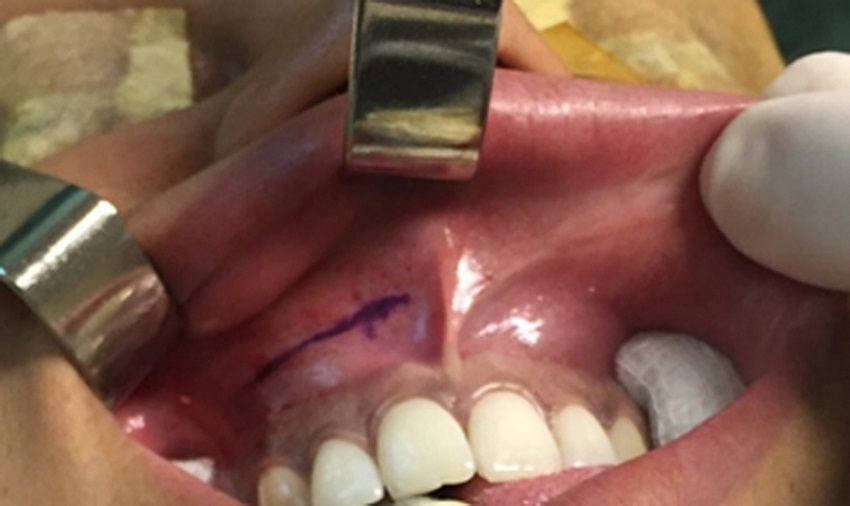

Surgical technique

Three months after being submitted to surgery, the patients returned and answered the NOSE questionnaire, to the same examiner, and were submitted to postoperative rhinomanometry with the same equipment, with and without vasoconstrictor agent.